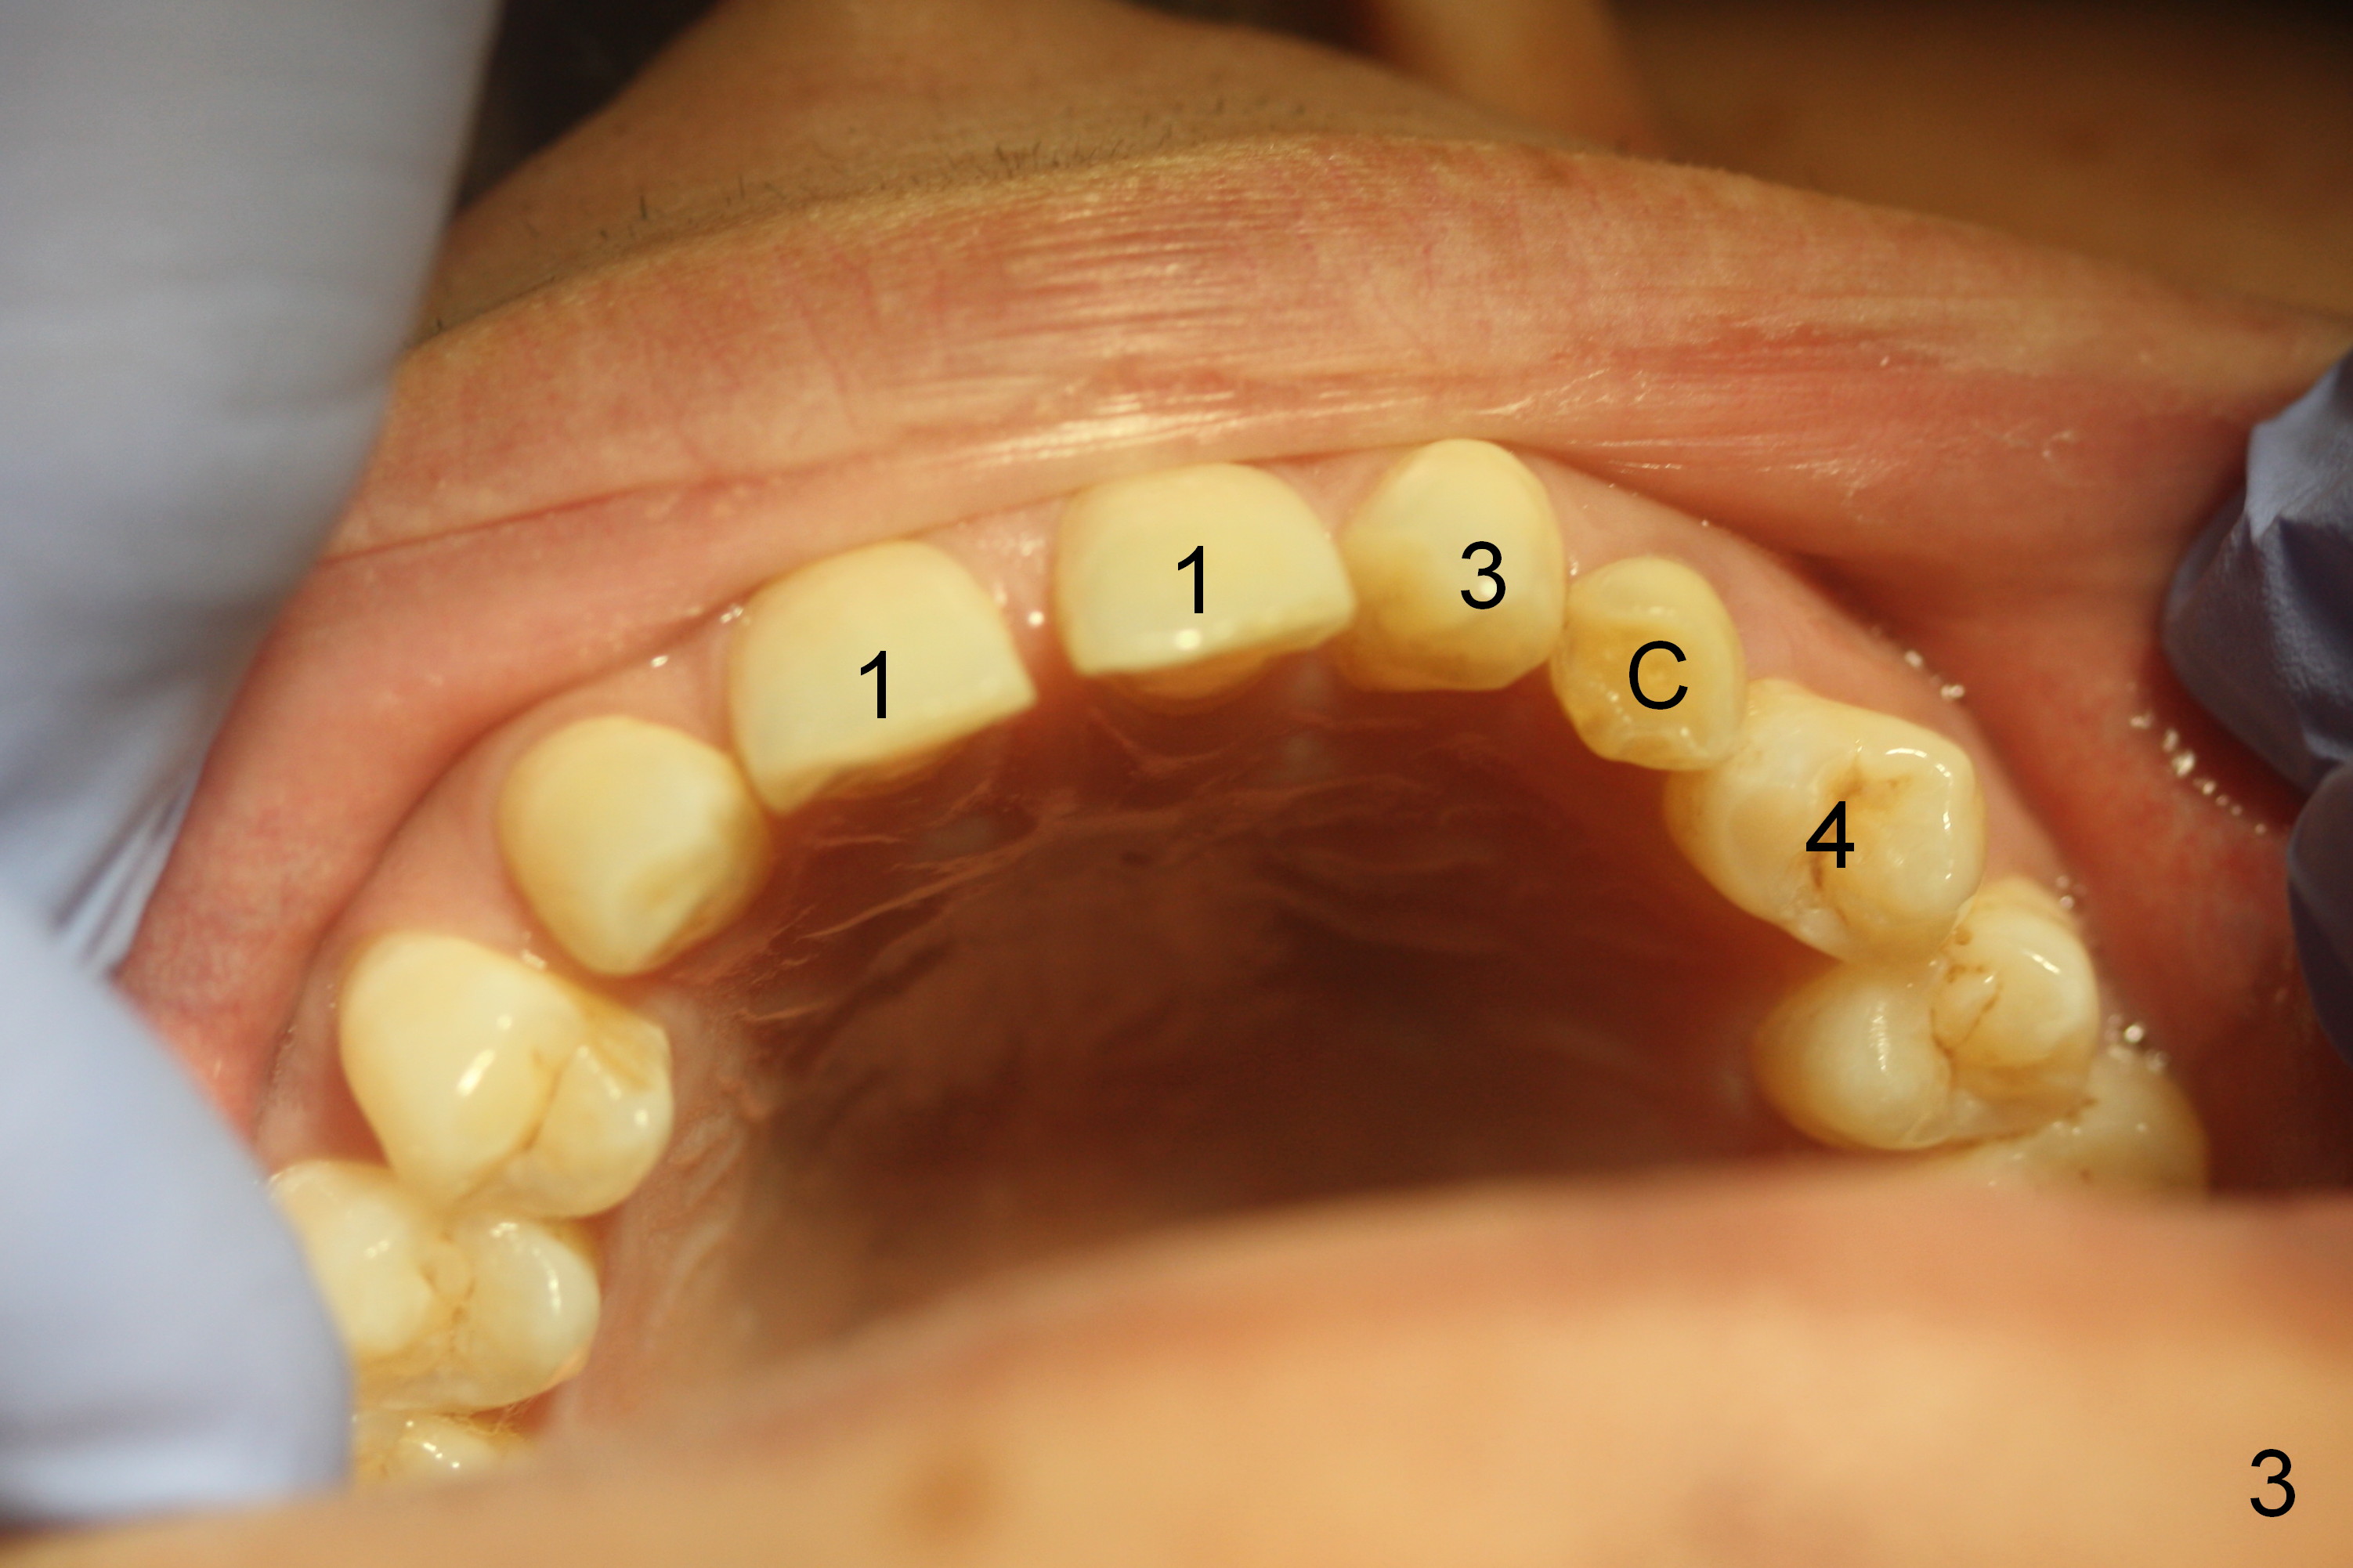

A 38-year-old man has congenitally missing laterals (Fig.1,2) with retention of a deciduous canine (Fig.2,3 C). UL 4 (upper left 1st bicuspid) rotates (Fig.3). LR7 has been extracted (Fig.4).

To improve cosmetics, extract the deciduous tooth (Fig.5), place brackets for the maxillary teeth (6-6), including a lingual button on UL4 to correct the rotation and distalize U3s (Fig.6), close the upper midline diastema and change the midline if needed (Fig.7) and finally place small-diameter implants at U2s (Fig.8 white circles).